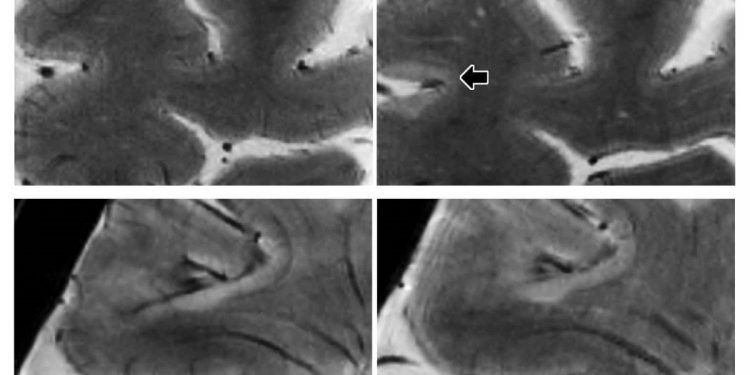

7Т МРТ в начале исследования (слева) и 1,5 года наблюдения (справа) у женщины с вторичным прогрессирующим РС, показывающим развитие двух внутрикортикальных поражений. Внизу: 7Т МРТ в начале исследования (слева) и 1,4 года наблюдения (справа) у женщины с рецидивирующим ремиттирующим РС, с новым лейкокортикальным поражением. (Предоставлено RSNA)

В течение периода наблюдения у двадцати пяти пациентов с РС развились новые корковые поражения. И 7Т МРТ обнаружил эти поражения чаще, чем МРТ нижнего поля, достигнутые в предыдущих исследованиях. В среднем число поражений, которые развивались в области коры, было более чем в два раза больше, чем в белом веществе.

Сканирование 7T показало, что повреждения коры головного мозга имеют тенденцию накапливаться в бороздках, которые представляют собой углубления на поверхности мозга. Исследователи также отметили, что общий объем корковых поражений был предиктором неврологической инвалидности как при базовой, так и последующей оценке. «Мы обнаружили, что эти поражения могут предсказать прогрессирование инвалидности больше, чем поражения белого вещества, которые являются типичными поражениями РС, которые мы изучали в течение многих лет», — говорит Майнеро.